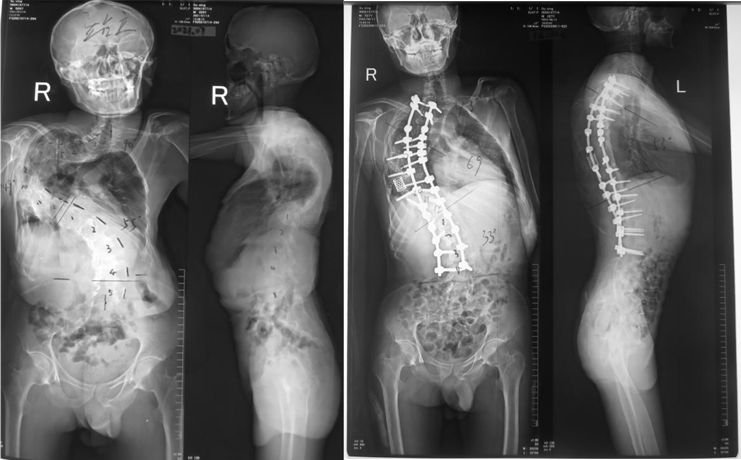

患者治疗前和治疗后的影像对比图